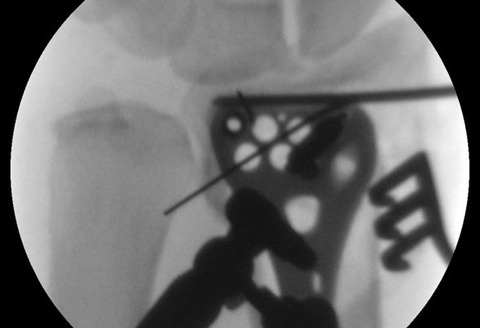

掌側プレートの遠位最尺側のスクリュー孔が正円になるように、手術台の傾きおよび前腕の回内外を調整します。上図では遠位最尺側のスクリュー孔に仮固定用スリーブを付けています。

スクリュー孔が正円になれば2次元でプレートの位置を調整します。掌側プレートの遠位最尺側のスクリュー孔を至適位置に誘導して、そのまま鉛直方向にドリリングするだけです。